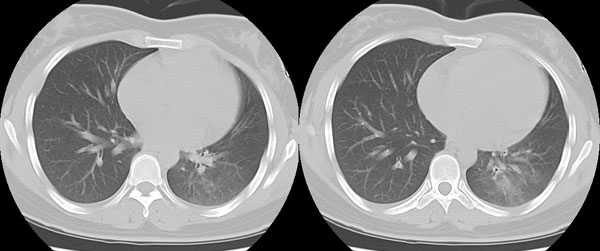

女性,25岁。反复咯血3年,再咯10天。外院x线胸片示:肺炎?支扩?

ct所见:左肺下叶基底段见大片状毛玻璃样改变,其内可见扩张细支气管。

胸部ct平扫所见:胸廓两侧欠对称,左侧略小,胸壁骨质结构完整。左肺下叶后、外基底段

见大片状毛玻璃样淡薄影,边缘渐淡,其内可见多个环形小囊状影。余肺野清晰,

肺纹理规则,气管支气管通畅,内壁光滑。心脏、大血管大小、形态、密度未见

明显异常,胸膜不厚、光滑,纵隔内未见明显肿大淋巴结。

诊断意见:左肺下叶大片状毛玻璃样淡薄影考虑支气管扩张伴出血。

见大片状毛玻璃样淡薄影,边缘渐淡,其内可见多个环形小囊状影。右肺野清晰,

诊断意见:左肺下叶支气管扩张伴出血。